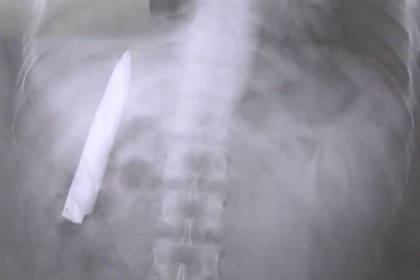

Se hizo una radiografía y le descubrieron un cuchillo en el pecho

Kent Ryan Tomao, de 25 años, es un ciudadano de Filipinas que se realizaba un examen preocupacional el martes pasado cuando de pronto, en medio de las pruebas, los médicos descubrieron en una de sus radiografía que el hombre tenía alojada, en el interior de su torso, una hoja de cuchillo.

Más tarde, los médicos se enterarían de que el joven había sido apuñalado por un grupo de delincuentes 14 meses atrás y, aparentemente, los profesionales de la salud que lo atendieron entonces cosieron la herida dejando la filosa hoja en el interior de Tomao.

El filipino, que fue atacado en la ciudad de Kidapawan cuando circulaba en su motocicleta, según él mismo narró al medio local ABS-CBN, descubrió junto a los médicos el filoso elemento que llevaba en su cuerpo cuando fue a realizarse un examen preocupacional para ingresar a un nuevo trabajo en la provincia de Agusan del Sur.

“Siempre me pregunté por qué sentía algo de dolor en mi pecho cuando el clima es frío, pero no tenía idea de que aquel cuchillazo seguía ahí adentro”, comentó Tomao al citado medio.

El joven filipino, que espera volver pronto al mismo centro de salud en Kidapawan para que le saquen el objeto, señaló que no tomará acciones legales contra los médicos que no se percataron de que tenía la hoja metálica en su interior, ni tampoco contra el centro de salud.